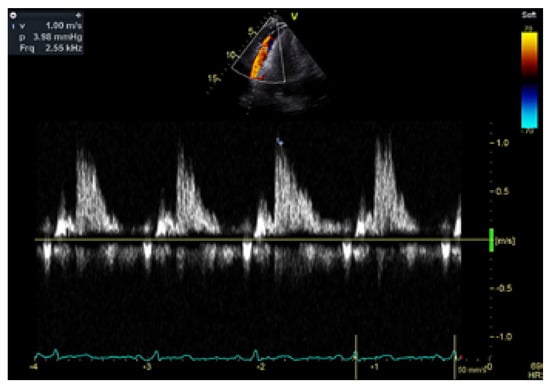

Transthoracic echocardiogram (TTE) confirmed a moderately sized circumferential serous pericardial effusion with no features of tamponade. Unusual prominent colour Doppler signals were seen within the pericardial space adjacent to the right ventricle free wall and directed towards the apex in systole (Figure 1, supplementary material: video clips). There was no evidence for communication with adjacent cardiac chambers. Flow signals were confirmed on pulsed-wave Doppler with maximal flow velocity of 100 cm/s. (Figure 2). Left ventricular dimensions and ejection fraction were normal while the right atrium and right ventricle were mildly dilated.

Figure 2. Pulsed-wave Doppler of the intrapericardial flow from a modified apical view. The sample volume is placed laterally to the right ventricle.